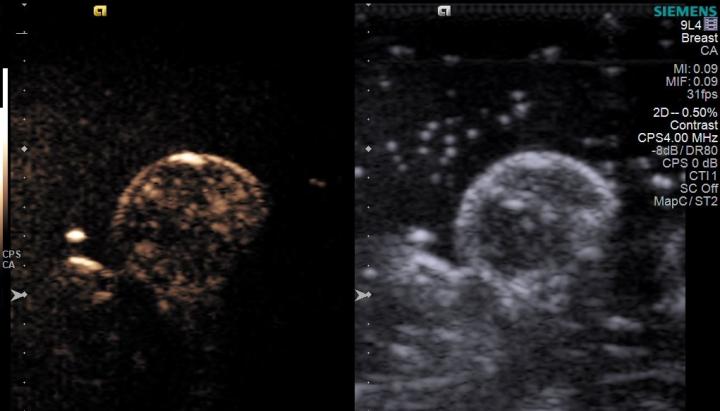

Figure 2 from Ultrasound-mediated microbubble destruction: a new method ...